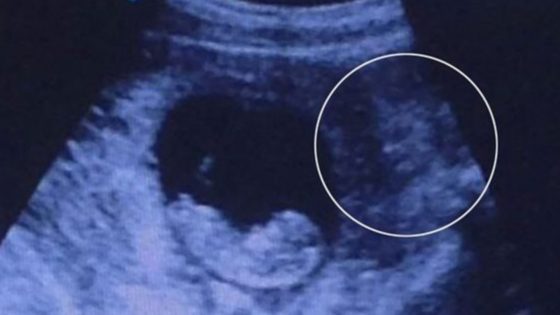

¿Un demonio en una ecografía?

En la imagen se puede apreciar un feto que tiene unas 9 semanas de gestación y a su lado aparece una figura con dos ojos y un cuerpo que parece estar observando al bebé. La imagen se convirtió en viral…